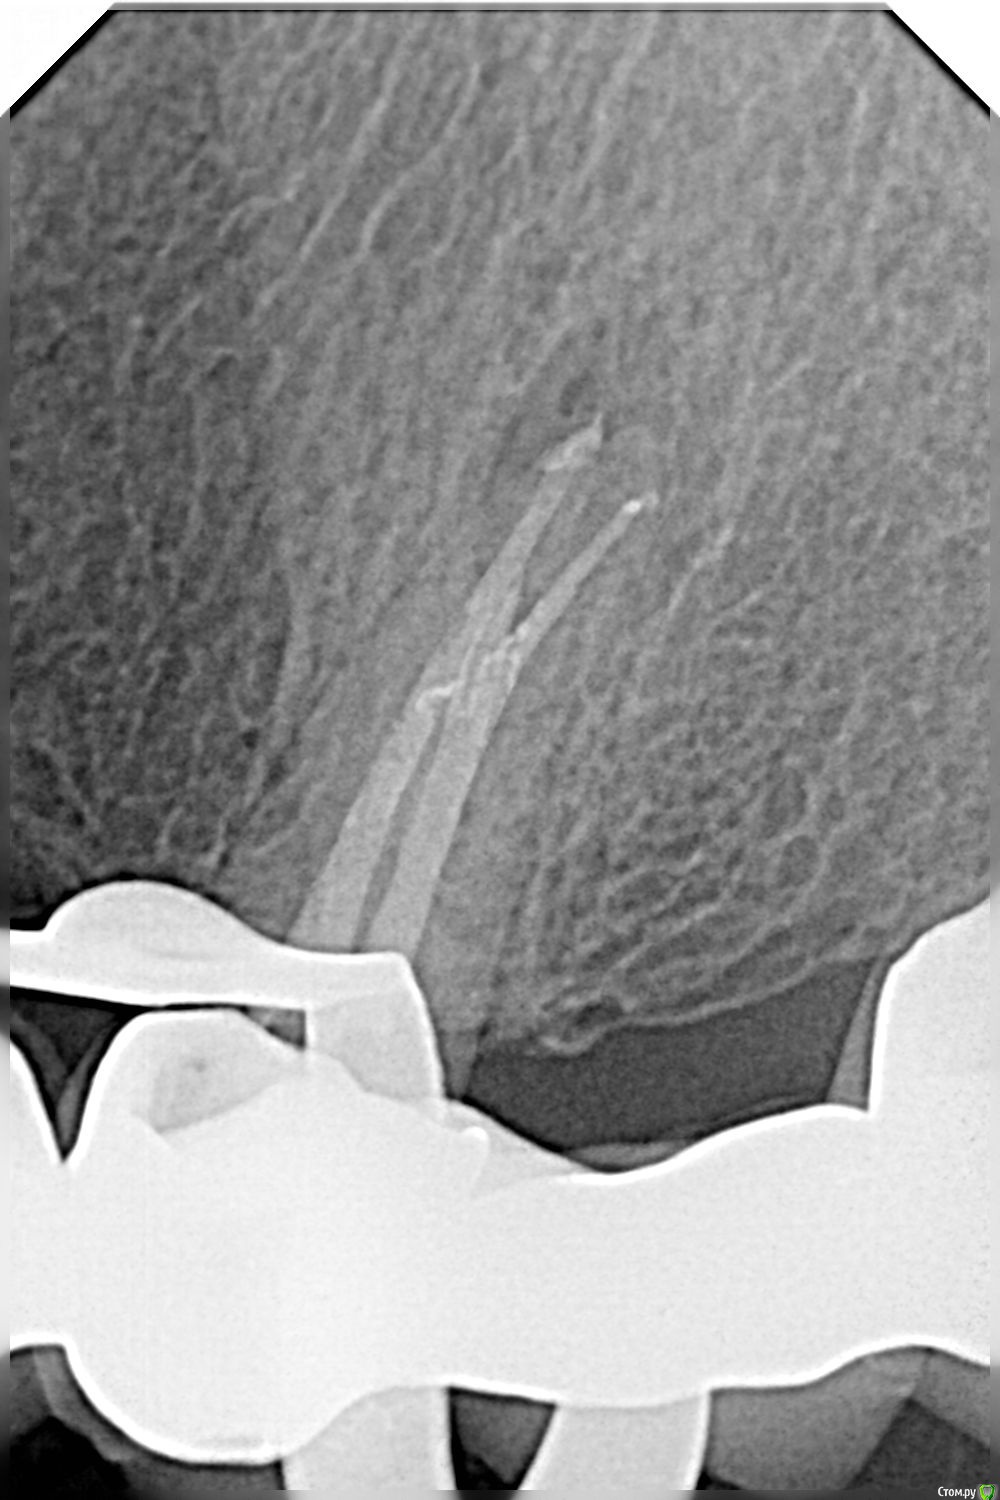

cor Опубликовано 16 октября, 2017 Поделиться Опубликовано 16 октября, 2017 Здравствуйте, уважаемые коллеги! Цикл передач "молодым, как я" продолжается. С последней темы я помолодел ещё года на 3-4, и решил написать. Давно не писал. А тут ещё и ДОК пост по доступам создал))) И так. Пациентка из области. Обострение хронического апикального периодонтита. Хороший человек, шикарная женщина в самом расцвете сил, и с цветущим синус-трактом... К сожалению КТ (хотя бы срезов) дома нет, кто очень захочет - пришлю. Жалобы: Постоянные ноющие боли, отделения гноя из прыщика на десне, "не могу жевать". Всё в течении месяца. Об -но: Конструкция МК (язык не поворачивается назвать мостовидный протез) с опорой на 27, 25, и.... 21. Плюс 11 консоль. Произведён и установлен очень добрым доктором 3 года тому назад. Прилегание отличное. И шатал я его и болтал, и прилегание в скоп смотрел - толку ноль, стоит как влитой. Долго рассказывал о возможных осложнениях, но снимать конструкцию категорически отказалась. Назначили встречу через 2 недели, что бы подумала. То ли я плохо обрисовал ужасы, то ли она не думала... решили лечить 25 через коронку. Я тоже добрый доктор) Когда такие работы вижу - всегда есть косяк. И тут был. Протез то сел как надо, но ортопед поправлял по прикусу, аж до металла Пилить керамику было жалко, через метал сделал доступ. В принципе, ни каких проблем с обработкой, если навык есть. Стандартный эндопротокол, и кальций на 2 недели. Пациентка приехала довольная - ничего не болит, свища нет.Пломбировались долго, там 6 тип по Вертучи был. И доступ не удобный)))) Шилдер. Ждем реколл через 6 месяцев. И так, молодые доктора! Какой урок извлёк я. Это единичные случаи, не надо так делать! Мне просто повезло. Там столько подводных камней, лучше не соваться. А если нет микроскопа, то лучше и не думать) А доктора по опытнее, поделитесь своим мнением, пожалуйста, стоит ли? ЗЫ: Сразу своё мнение скажу. Я против такого лечения (теперь). 4 Ссылка на комментарий